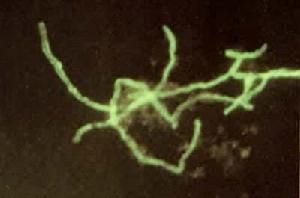

在病灶和膿樣物質中形成硫磺樣顆粒,菌體多呈菊花狀排列,用蘇木紫伊紅染色,菌體呈紫色,棒狀末端為紅色,人工培養較困難(見彩圖)。專性厭氧,在腦心浸液瓊脂培養基上35~37℃培養7~14天后,形成直徑0.5~3毫米的粗糙型不規則菌落。DNA中的G+C克分子含量為60%。一般為內源性感染,當局部抵抗力降低或全身免疫力受抑制而又有局部損傷時,易誘發以慢性膿腫和多發性瘺管為特徵的放線菌病。所形成的抗體可與分枝桿菌、棒狀桿菌有交叉反應。可用磺胺、青黴素和四環素等治療。

專性厭氧菌。DNA中的G+C克分子含量為63%。寄生於動物和人的消化道中,特別是口腔、咽部和扁桃體,還未在自然界發現。其在口頰、齒齦等部位發生損傷時侵入組織內,引起放線菌病(化膿、肉牙腫、骨質糜欄等,可轉移至肝、肺)。本菌因生長條件的不同而呈現多種形態。在病灶膿液中形成淡黃色硫磺樣顆粒,用載玻片壓碎進行鏡檢時,發現其中心繫由革蘭氏陽性的分枝菌絲和一些短桿狀或球狀的菌體組成,四周為呈放射狀排列的革蘭氏陰性棍棒狀菌體。